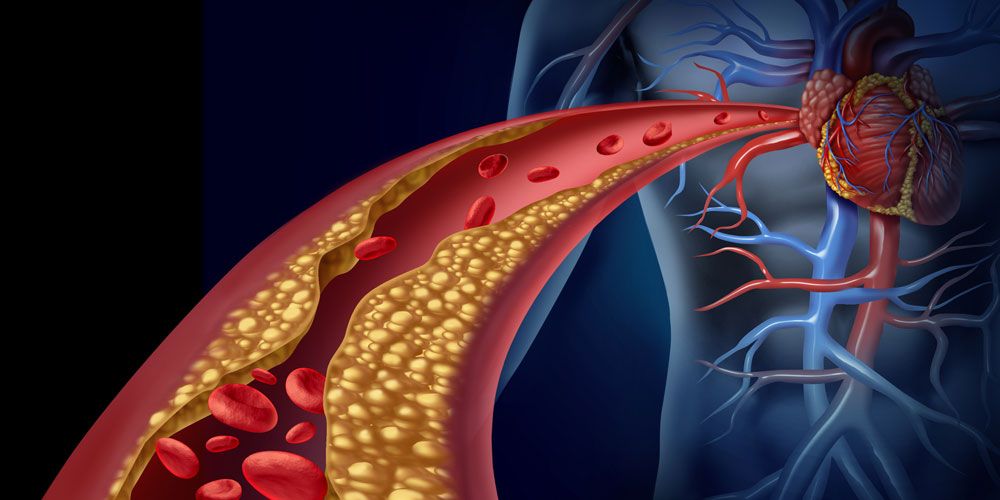

Η στεφανιαία νόσος είναι μια χρόνια πάθηση που επηρεάζει τις στεφανιαίες αρτηρίες, δηλαδή τα αγγεία που τροφοδοτούν την καρδιά με αίμα και οξυγόνο.

Οι δυσλιπιδαιμίες αφορούν διαταραχές στα επίπεδα των λιπιδίων του αίματος, όπως η αυξημένη χοληστερόλη και τα τριγλυκερίδια.